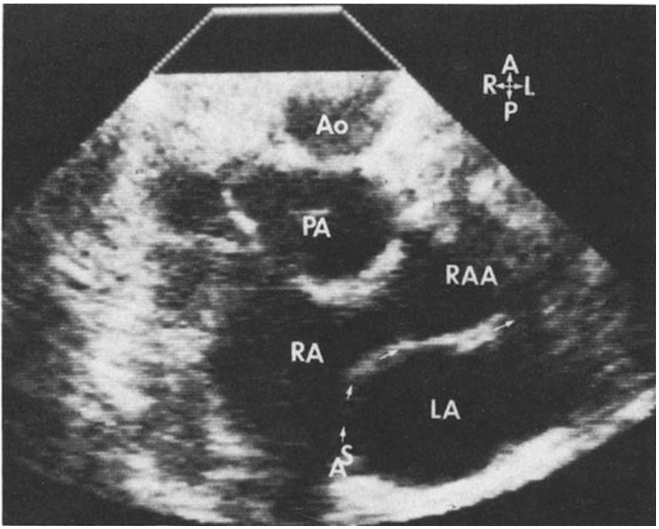

A chest X-ray revealed heart and stomach gas on the right side (Figure 1). A conventional transthoracic echocardiogram revealed dextrocardia without another abnormalities (Figure 2). A computerized tomography of the abdomen was performed and showed the liver on the left side, spleen and stomach on the right side. No other congenital malformations were found (Figure 3). Currently, the patient is 16 years old and under periodic systematic control at the Hematology and Cardiology services.

Figure 2: Echocardiogram revealing dextrocardia.

Ao: Aorta; PA: Pulmonary Artery; RA: Right Atrium; RAA: Right Aortic Arc; LA: Left Atrium.